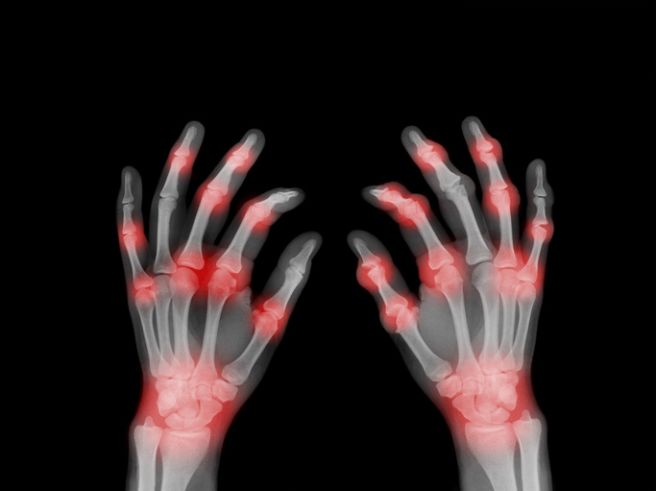

오늘은 우리 몸의 자가면역 질환 중 하나인 류마티스 관절염의 초기 증상에 대해 이야기하려 합니다. 류마티스 관절염은 면역 체계가 자신의 관절을 공격하여 염증을 일으키는 질환으로, 조기에 발견하지 못하면 관절이 파괴되어 영구적인 변형을 초래할 수 있습니다.

류마티스 관절염은 보통 여러 관절에서 동시에 증상이 나타나며, 대칭적으로 발생하는 경향이 있습니다. 다음은 류마티스 관절염 환자들이 흔히 겪는 10가지 주요 초기 증상입니다.

류마티스 관절염 초기증상 - 관절 통증이 양쪽에서 대칭적으로 발생

- 설명: 류마티스 관절염은 오른쪽 손가락 관절이 아프면 왼쪽 손가락 관절도 함께 아픈 것처럼, 몸의 양쪽에서 대칭적으로 증상이 나타나는 경우가 많습니다.